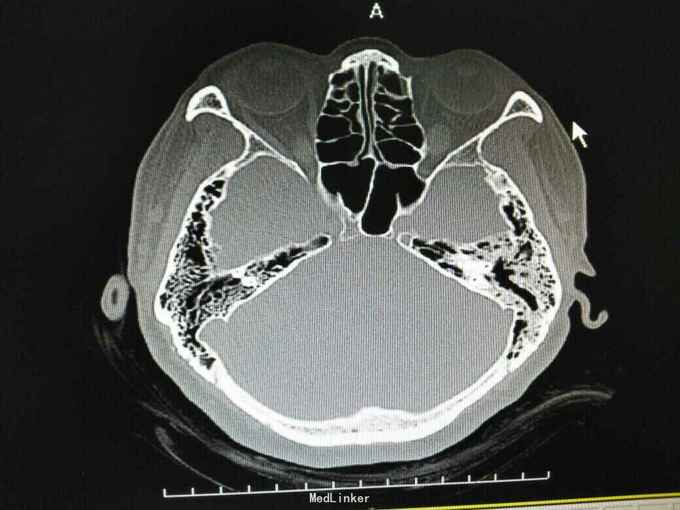

外耳道胆脂瘤,并 分泌性中耳炎? 胆固醇肉芽肿?

患者女性,47岁,以听力下降一周为主诉入院。 就诊后见外耳道后壁缺损,鼓室內积液,给予抗炎治疗后,鼓室內积液由缺损外耳道排出,呈棕褐色。 辅助检查:纯音听阈基本无听力损失。 诊断 外耳道胆脂瘤,并 分泌性中耳炎? 胆固醇肉芽肿? 治疗: 1.乳突根治术?乳突蜂房气化非常好,比较难做。 2.外耳道成型、后壁修补?